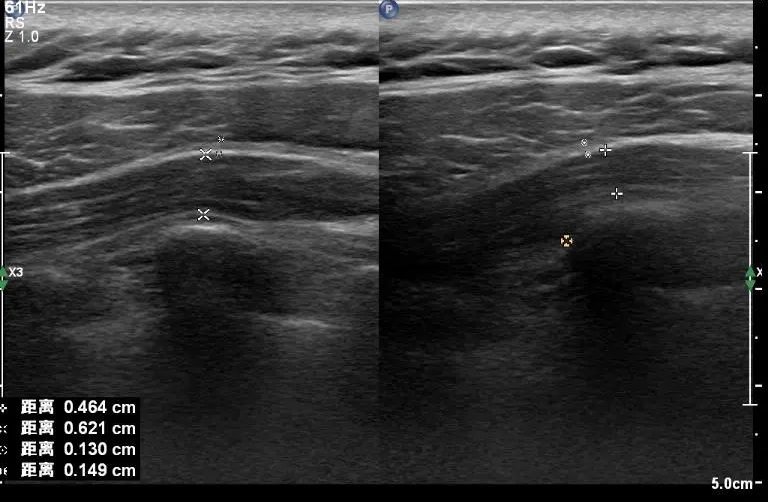

图一:膝关节半月板损伤

图二:腕管综合症